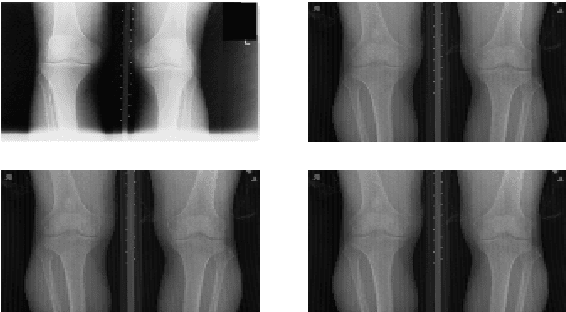

This paper proposes a new approach to automatically quantify the severity of knee osteoarthritis (OA) from radiographs using deep convolutional neural networks (CNN). Clinically, knee OA severity is assessed using Kellgren \& Lawrence (KL) grades, a five point scale. Previous work on automatically predicting KL grades from radiograph images were based on training shallow classifiers using a variety of hand engineered features. We demonstrate that classification accuracy can be significantly improved using deep convolutional neural network models pre-trained on ImageNet and fine-tuned on knee OA images. Furthermore, we argue that it is more appropriate to assess the accuracy of automatic knee OA severity predictions using a continuous distance-based evaluation metric like mean squared error than it is to use classification accuracy. This leads to the formulation of the prediction of KL grades as a regression problem and further improves accuracy. Results on a dataset of X-ray images and KL grades from the Osteoarthritis Initiative (OAI) show a sizable improvement over the current state-of-the-art.